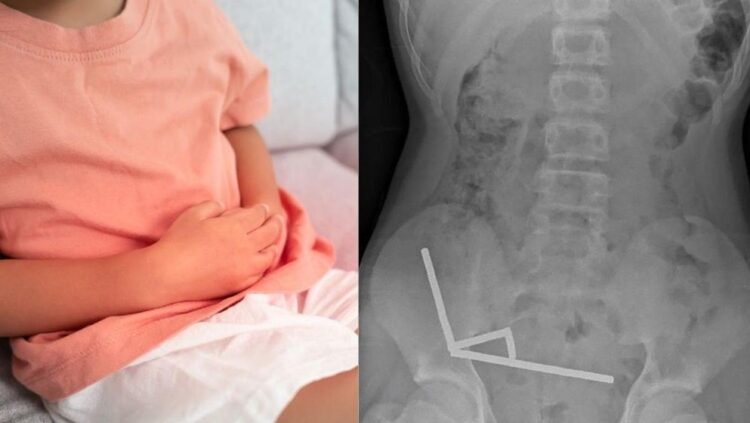

প্রতিবেদনে বলা হয়েছে, চার দিন ধরে পেটে তীব্র ব্যথা নিয়ে কিশোরটিকে নর্থ আইল্যান্ডের টরাঙ্গা হাসপাতালে ভর্তি করা হয়।নিউজিল্যান্ড মেডিকেল জার্নালে প্রকাশিত হাসপাতালের চিকিৎসকদের প্রতিবেদন অনুযায়ী, কিশোরটি ভর্তির প্রায় এক সপ্তাহ আগে প্রায় ৮০ থেকে ১০০টি (৫ x ২ মিলিমিটার আকারের) শক্তিশালী নিওডিমিয়াম চুম্বক গিলে ফেলেছিল। এক্স-রে রিপোর্টে দেখা যায়, এই চুম্বকগুলো তার অন্ত্রের ভেতরে চারটি সরলরেখায় জড়ো হয়েছে। চিকিৎসকেরা জানান, চুম্বকীয় শক্তির কারণে অন্ত্রের বিভিন্ন অংশ একসঙ্গে আটকে যাওয়ায় তীব্র চাপ সৃষ্টি হয়, যার ফলে টিস্যু মারা যায়।

সার্জনরা দ্রুত অপারেশন করে মৃত টিস্যু অপসারণ করেন এবং আটকে থাকা চুম্বকগুলো বের করে আনেন। চিকিৎসকেরা নিশ্চিত করেন, কিশোরটির ক্ষুদ্রান্ত্র এবং বৃহদন্ত্রের অংশ ক্যাসেম-এর চারটি জায়গায় টিস্যু মারা গিয়েছিল। আট দিন হাসপাতালে থাকার পর শিশুটিকে ছাড়পত্র দেওয়া হয়।